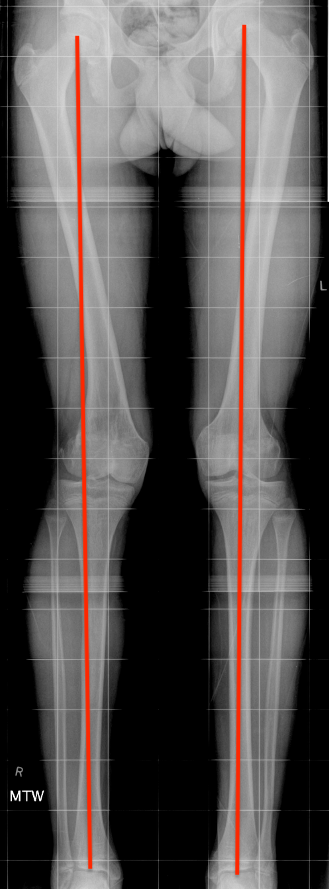

Complete growth arrest / Leg length discrepancy

SH1SH1LLD

Monitor 6 monthly

- plot short and long leg lengths on Mosely chart

- distal femur contributes 9 mm / year

LLDLLD

Manage LLD as per predicted difference

- contralateral femoral epiphysiodesis +/- femoral lengthening